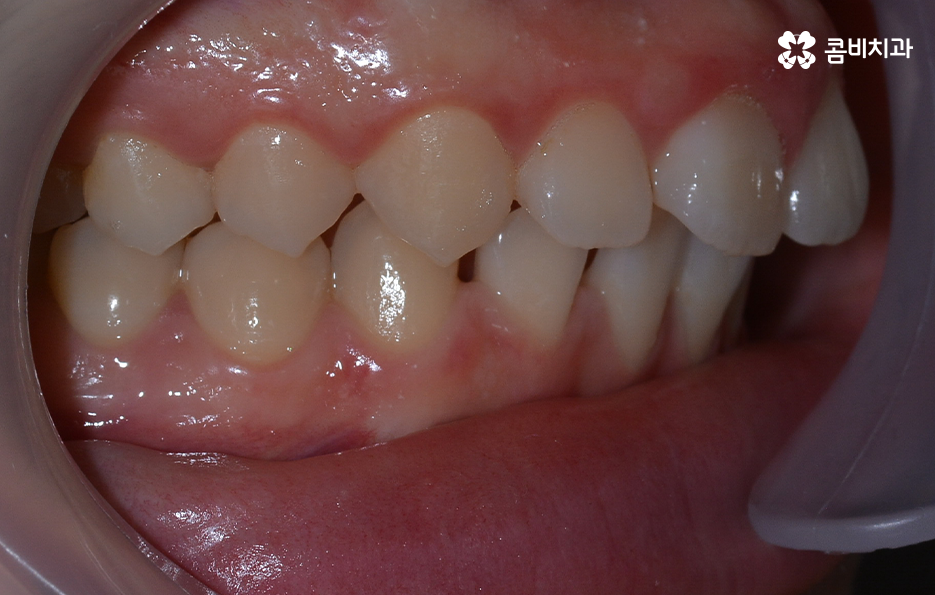

오늘 소개드릴 케이스의 경우 아랫니가 비교적 작기 때문에 교정을 통해 모아주고 윗니의 경우 측면으로 볼 때 더 잘 느껴지겠지만 다소 돌출된 상태이기 때문에 윗니는 발치를 통해 치아 이동 공간을 확보하여 돌출된 앞니를 안쪽으로 모아준 사례로 볼 수 있는데요

아랫니의 경우 치아 사이가 벌어져 있기 때문에 치아를 이동시킬 수 있는 공간이 이미 확보된 상태이고 윗니는 다소 돌출된 앞니를 안쪽으로 들어오게 하면서 심미선을 얼굴형에 조화롭게 맞출 수 있으며 그와 동시에 윗니와 아랫니의 교합도 고려한 치료 계획을 세운 것으로 간단하게 말씀드릴 수 있어요